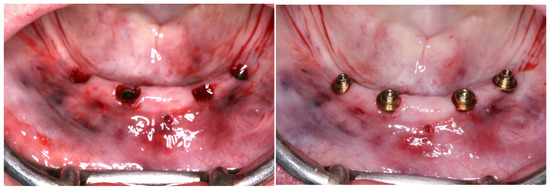

2. Case Report